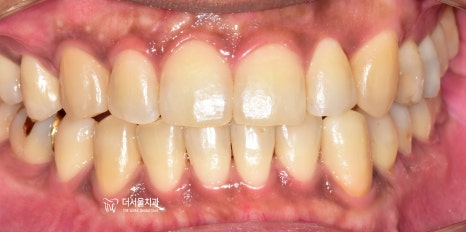

『초진 사진』

정면과 측면에서의 모습입니다.

치열의 불규칙성이 한 눈에 들어옵니다.

정면에서 보는 안모사진을 보면,

얼굴의 중신선과 앞니들이

서로 일치하지 않는것을 볼 수 있습니다.